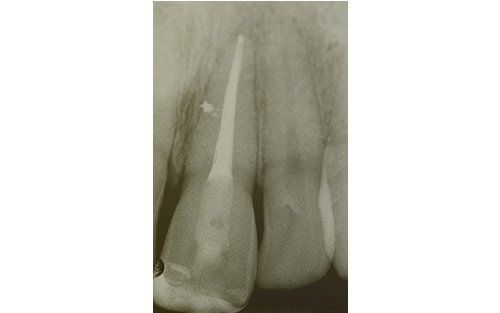

Frequenti, in età pediatrica, sono i traumi (sportivi e non). Come conseguenza i denti anteriori superiori (ovvero gli incisivi) sono i più esposti all’evento che può esitare in una frattura della corona con o senza il coinvolgimento della polpa, nella necrosi del dente (che può avvenire, più facilmente, senza alcuna frattura della corona dentale), oppure in quel panel di complicanze che vanno dalla lussazione ai traumi intrusivi o estrusivi, fino all’ avulsione, cioè la fuoriuscita completa del dente dall’alveolo.

Anche nel caso dell’avulsione, ovvero della fuoriuscita del dente, è importante conservare l’elemento nel latte o in soluzione fisiologica e recarsi davvero “di corsa” dal dentista: entro i primi 60 minuti ci sono buone probabilità che il riposizionamento del dente sia coronato da successo a medio-lungo termine.